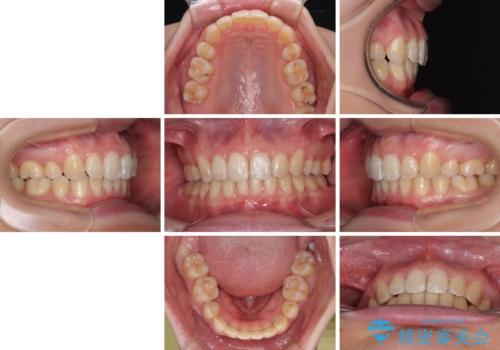

上下の抜歯位置を変えることで、左右ともに理想的な咬み合わせを達成することができました。

横顔の印象はほとんど変わらないものの、唇を閉じたときに前に出ていた下唇が、治療後には少し下がった状態に仕上げることができました。